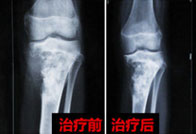

38岁的晴天霹雳:胚胎型横纹肌肉瘤

我今年38岁,2016年前的人生还算顺利,娶妻生子,父母健在,一名事业单位员工,俗称铁饭碗。本以为就这么稳稳当当的过一辈子。但一个晴天霹雳,胚胎型横纹肌肉瘤让我不知所措。 [阅读全文]